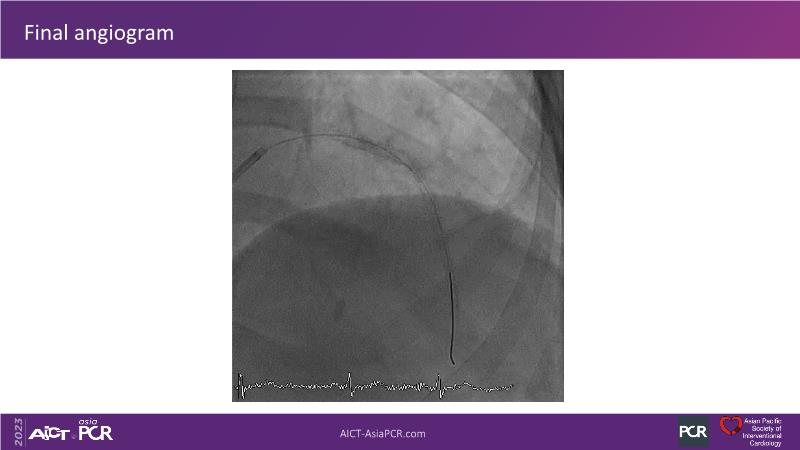

This session is recommended for you if you are seeking insights into the advantages of using IVUS imaging over visual assessment for better outcomes in left main bifurcation procedures. Discuss with experts the benefits of using RotaCUT in lesion preparation for left main bifurcation and explore the impact of high radial strength stents on the procedure's success.